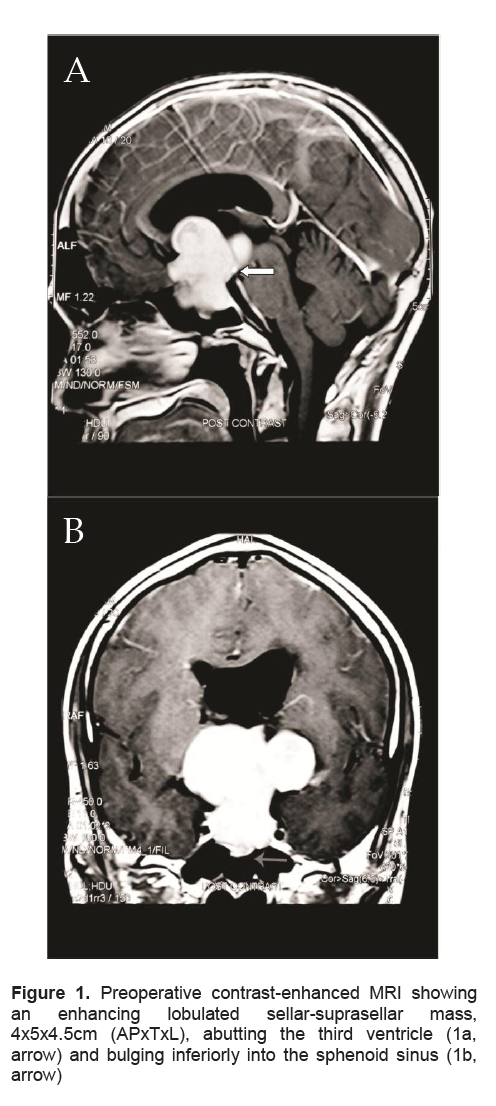

A 38-year-old male presented in another institution because of generalized seizure lasting for 2 minutes. A week prior to the event, the patient complained of generalized weakness, fatigue, anorexia, nausea and vomiting. For the past 5 years, he claimed intermittent episodes of frontal headaches which were later associated with blurring of vision especially at the right lateral area 2 years ago. At the emergency room, the patient was initially man aged as a case of adrenal insufficiency. Precluding hormonal studies, an imaging study was done. Magnetic Resonance Imaging (MRI) of the pituitary revealed a 4.0 x 5.0 x 4.5 cm sellar-suprasellar mass (Figure 1). Cortisol was low at 2.8ug/dl. ACTH was inappropriately normal for a low cortisol. Prolactin was within normal (Table 2). Thyroid function tests revealed elevated total hormones and elevated TSH, but repeat testing using free hormones revealed a low normal FT4 (free T4), a slightly low FT3 (free T3) and still an inappropriately elevated TSH (Table 1). Other hormonal work-ups concluded hypogonadotropic hypogonadism (Table 2). Visual field studies revealed bilateral hemianopsia. Patient was started on steroids (prednisone) and anti-seizure medication (levetiracetam). The symptoms of generalized weakness, fatigue, anorexia, nausea and vomiting resolved immediately after initiating the steroids. This confirmed concluded the diagnosis of adrenal insufficiency secondary to hypopituitarism secondary to a pituitary macroadenoma. The seizure did not recur. A repeat thyroid function test was done a month later which revealed a high normal TSH and an elevated FT4 (Table 1). However, these derangements pointing to a probable central hyperthyroidism were not taken into consideration. Patient eventually underwent craniotomy with excision of the tumor with an aggregate measurement of 3.0 x 2.5 x 0.5cm and a pathological diagnosis of a pituitary adenoma (Figure 2a). Further excision was not possible because its consistency was firm to harn and further excision could further damage some vital tissues. Perioperative course was uneventful. Post-operative CT-scan revealed a residual mass measuring 3.1 x 4.4 x 3.0 cm (Figure 3). Succeeding follow-ups were done in our institution. Patient denied recurrence of the initial symptoms except for the blurring of vision at the right lateral area, although he claimed improvement.

Figure 1. Preoperative contrast-enhanced MRI showing an enhancing lobulated sellar-suprasellar mass, 4x5x4.5cm (APxTxL), abutting the third ventricle (1a, arrow) and bulging inferiorly into the sphenoid sinus (1b, arrow)